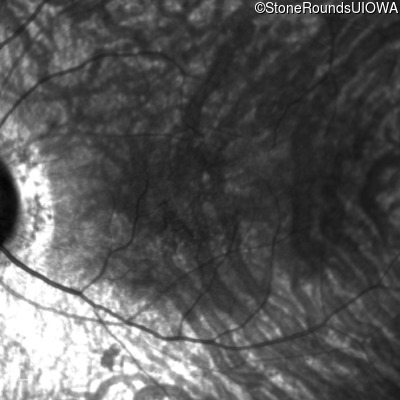

Infrared Fundus Photograph - Left - 20/50

Exemplar